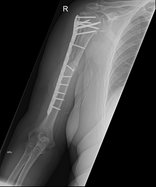

Humeruskopffraktur

Ein Bruch des Oberarmkopfes entsteht bei jüngeren Patienten meist durch einen direkten Anprall auf die Schulter beim Sport, oder bei Verkehrsunfällen. Bei älteren Patienten stehen die Brüche des Oberarmkopfes meist im Zusammenhang mit einer schlechteren Knochensubstanz, wie. z.B. bei einer Osteoporose und können auch schon bei kleineren Traumata entstehen.

Im Beispiel sehen sie einen 4 Teile Bruch, mit Fraktur des großen und kleinen Rollhügels sowie einem Bruch durch den chirurgischen Hals des Knochens (subcapitaler Bruch).

Dislozierte oder offene Brüche sowie begleitende Gefäß- oder Nervenverletzungen bedürfen einer zügigen operativen Versorgung. Dabei stehen dem Schulterspezialisten verschiedene Hilfsmittel, wie Platten, Schrauben oder Nägel, aber auch künstliche Gelenke zur Verfügung. Je nach Verletzung werden die für Sie benötigten speziellen Instrumente eingesetzt.